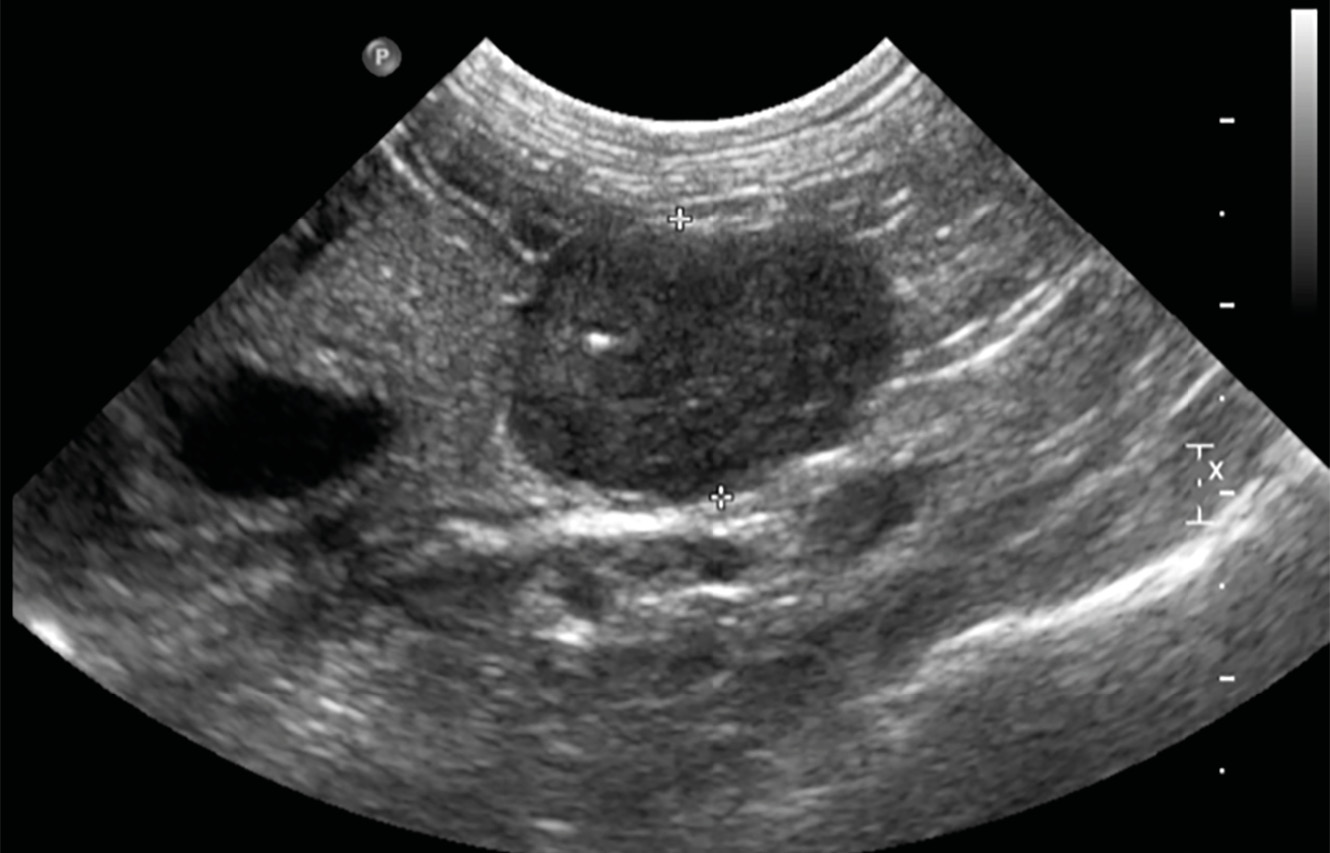

La ecografía abdominal es una técnica accesible que permite identificar masas adrenales, aunque es dependiente del operador, del paciente y del equipo disponible.

En los casos descritos de HAP felino por una masa adrenal en los que se realizó una ecografía se encontró adrenomegalia en todos los gatos con diámetros que oscilaban entre 1 y 5 cm (imagen 3). La glándula contralateral puede ser evidente y tener un aspecto normal, o puede no visualizarse. Es importante intentar visualizar ambas glándulas adrenales para determinar si el tumor es unilateral, bilateral o si es posible que se trate de una hiperplasia bilateral de la zona glomerulosa. Además, en gatos con masas adrenales y atrofia de la glándula adrenal contralateral se debería considerar la secreción concomitante de corticosteroides.

La ecografía adrenal en gatos con hiperplasia bilateral de la zona glomerulosa puede no mostrar cambios detectables, o bien mostrar cambios sutiles e inespecíficos como aumento de la ecogenicidad adrenal, áreas de calcificación o engrosamiento de un polo de una o ambas glándulas adrenales. La ecografía también puede determinar si hay invasión de estructuras adyacentes, como la vena cava caudal.